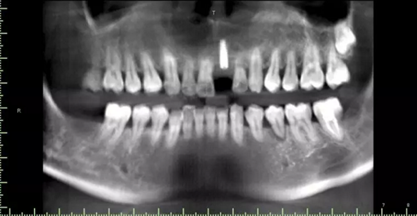

1.術(shù)前CT

術(shù)后CT